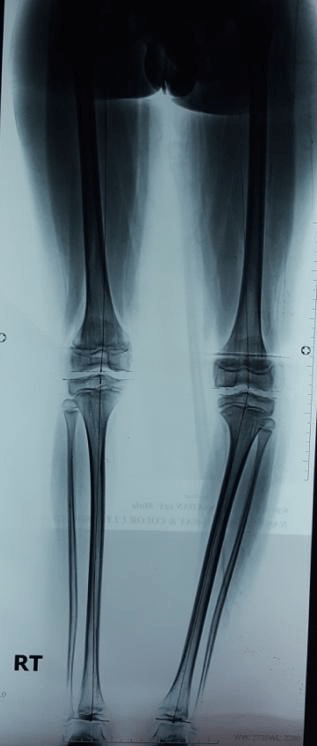

Guided growth for unilateral bowleg due to deformity in leg

Pre op deformity: Note the left leg showing bowleg deformity

Pre-operative standing alignment X-ray confirming deformity in leg bone tibia on the left side.